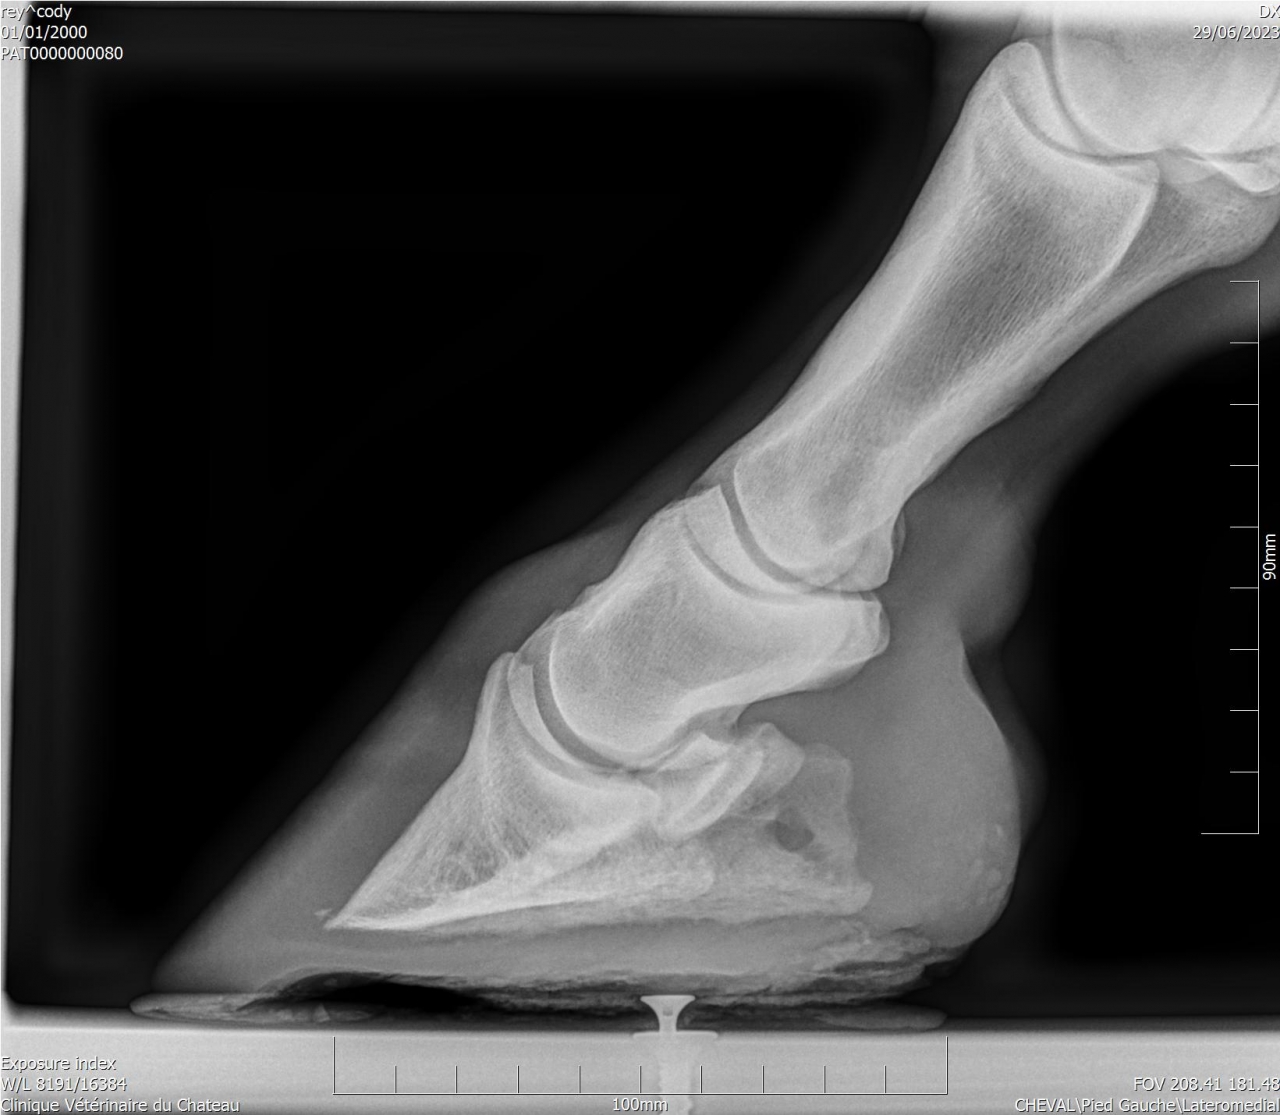

| Dire merci | Je fais un sujet à part pour donner des nouvelles ![]() J’ai fait passer un autre véto pour un 2ème avis. Au début il pensait à un abcès très profond, emplacement détecté avec la pince à sonder. Il a ensuite fait des radios : si j’ai bien compris, la 3ème phalange appuie sur la sole Il y a également de l’arthrose ... Le traitement pour le moment : anti inflammatoires et hipposandales en attendant de pouvoir referrer, et changer de maréchal ferrant. Apparemment il existerait un traitement au laser, le véto va se renseigner. Cody a fait une fourbure l’année dernière, des radios ont été faites à ce moment. J’ai aussi refait des radios de contrôle cette année, il restait une légère bascule de P3. |

| Dire merci | Il y a quand même de jolies bascules, il doit pas être bien c'est sûre. Les degrés de bascule t'ont été donnés? Pour moi il y a urgence à trouver un bon maréchal, qui va travailler avec les radios, mais ça va mettre plusieurs mois à "rentrer dans l'ordre" si pas d'autres crises inflammatoires et nouvelles bascules, ça se compte en plusieurs mois voir année. Et malheureusement une surveillance constante. |

| Dire merci | J'ai eu le collègue du véto au téléphone : pas de risque immédiat que la phalange perce la sole il reste 1 cm. La 3ème phalange appuie sur la sole, il y a nécrose. La pointe ne risque pas de casser. Je viens de commander 2 hipposandales Cloud. Il faut que je trouve quelqu'un pour déferrer Cody et éventuellement parer l’autre antérieur. Message édité le 22/11/24 à 20:31 |

| Dire merci | Voici les dernières radios :![]() ![]() ![]() |